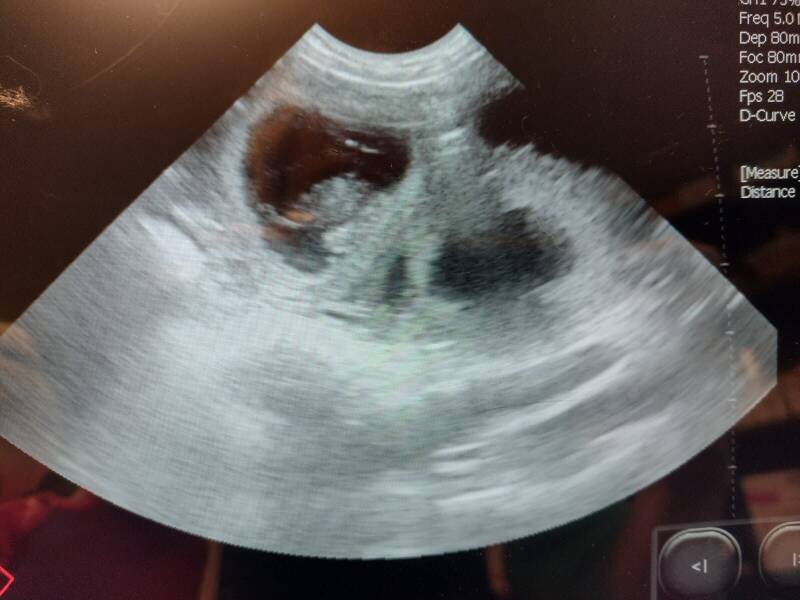

9 pups

4 reuen - 2 x zwart + 2 x bruin

5 teef - 3 x zwart + 2 x bruin